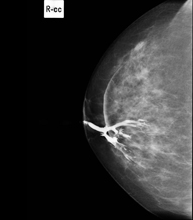

Mamografía

Los estudios de Mamografía obtienen imágenes generadas a partir de rayos X de muy baja dosis, permitiendo detectar las diversas patologías de los tejidos mamarios (en especial el cáncer de mama), tanto para cribado (screening) ginecológico como para diagnóstico dirigido. La mamografía puede ser intervencionista con punción de quistes, biopsia estereotáxica, marcaje prequirúrgico y galactografía.

Mamografía digitalizada

La mamografía digitalizada es una técnica innovadora que permite estudiar la mama con una dosis baja de radiación, reduciéndola respecto al empleo de mamografía convencional. La imagen se digitaliza a partir de unos chasis especiales llamados CR. Gracias a estas técnicas de digitalización se obtienen excelentes imágenes, sobre todo en mamas de difícil estudio como las glandulares que se presentan en la mamografía como una mama densa, detectando en este grupo de pacientes mejor las tumoraciones.